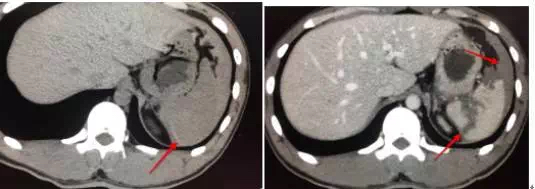

23岁男,车祸入院,平扫很可能漏掉,调节窄窗宽,密度不均匀,增强很明显撕裂伤。

3.轻微撕裂伤,平扫难以发现,要做增强,就算夜班,也要做增强。

18岁男,车祸入院,平扫脾周积液,高密度,边缘见条状高密度影,脾脏积血(看到此征象,夜班急诊的时候千万要警惕脾破裂,及时提示临床医生,患者随时都有可能大出血休克)。CT增强可见脾破裂,破口及积液显示较平扫清晰。